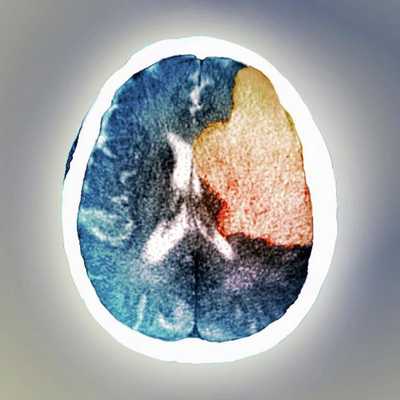

Современной медициной бредовое расстройство рассматривается как расстройство головного мозга. В пользу этого говорит тот факт, что бредовые идеи могут развиваться вследствие токсических или метаболических нарушений, нейродегенеративных заболеваний (связанных с гибелью нервных клеток), опухолей или инсультов. В таком случае бредовые идеи будут называться вторичными, так как они развиваются на фоне другой (основной) болезни.

Ряд клинических исследований, изучавших органические психозы у пациентов с очаговыми инсультами, а затем новейшие нейровизуализационные исследованиях пациентов с бредовыми идеями, выявили критическую роль правой латеральной префронтальной коры в развитии бреда [6] .

Анализ клинических случаев пациентов с очаговыми инсультами показал, что бред развивается после одностороннего повреждения правого полушария мозга. Однако при этом у большинства пациентов с инсультом в правом полушарии бредовое расстройство всё же не развивалось. Уже позже благодаря расширенному анализу нейровизуализационных исследований стало известно, что бредовые идеи у людей с очаговым инсультом связаны именно с поражением правой латеральной префронтальной коры или её областью.

До конца не выяснено, чем именно обусловлена органическая бредовая симптоматика. Определенный вклад вносит двусторонняя наследственная отягощенность (по шизофрении, эпилепсии) и поражение специфических мозговых структур. Патогенетической основой органического шизофреноподобного расстройства чаще всего являются очаговые нарушения височных, теменных и лобных зон мозга. Для эпилепсии характерна височная локализация, для энцефалитов и других нейроинфекций - височная и теменная. Поражение височно-лобных областей проявляется бредом в сочетании с галлюцинациями (бред первичен, не зависит от обманов восприятия), нарушением контроля поведения.